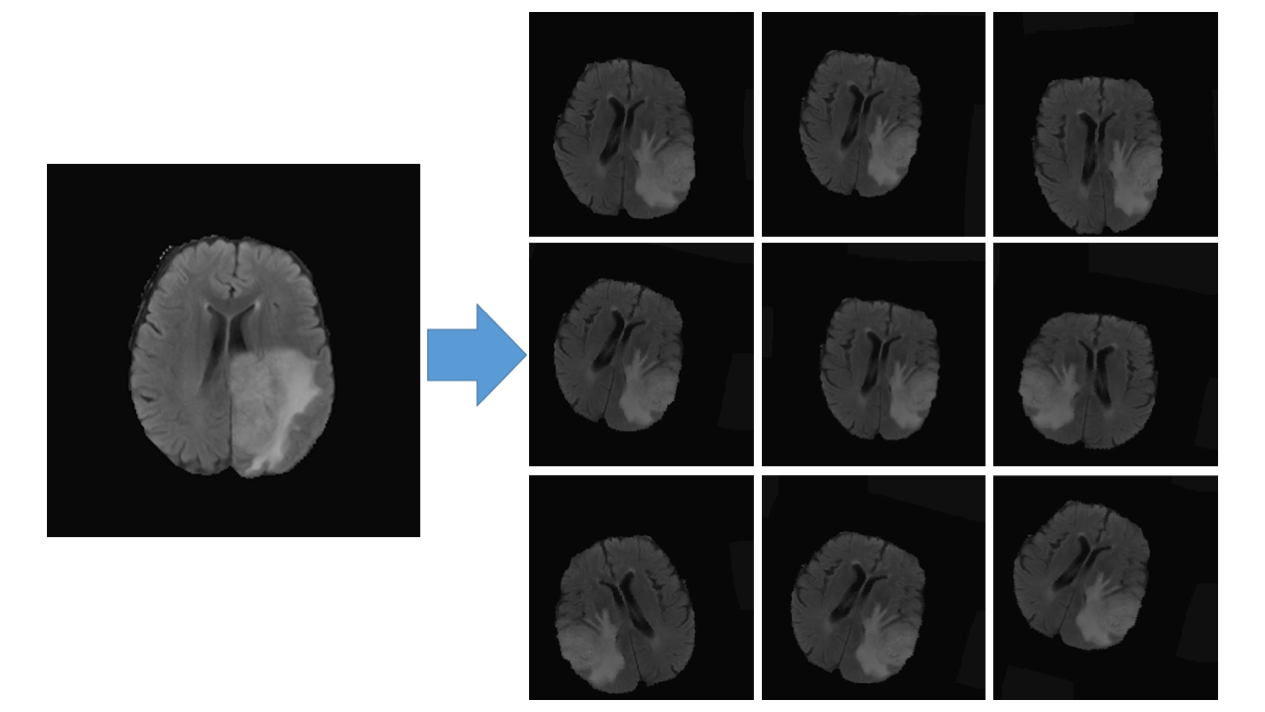

数据增强:包括随机左右翻转、旋转、位移、剪切、缩放和最重要的 弹性变换,详见论文 "Automatic Brain Tumor Detection and Segmentation Using U-Net Based Fully Convolutional Networks"。

图2:数据增强